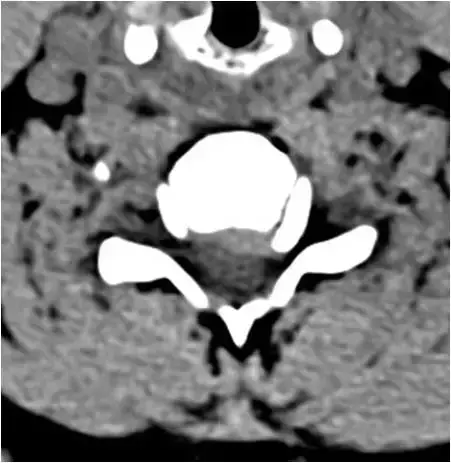

图23:下颈椎的轴向截面。广泛的骨赘形成和右钩椎关节肥大。硬膜囊颈髓的前部受压。确定脊柱狭窄。

图24:下颈椎的轴向截面。骨窗。与图像23相同的患者和相同水平。广泛的骨赘形成和右钩椎关节肥大。硬膜囊颈髓的前部受压。确定脊柱狭窄。